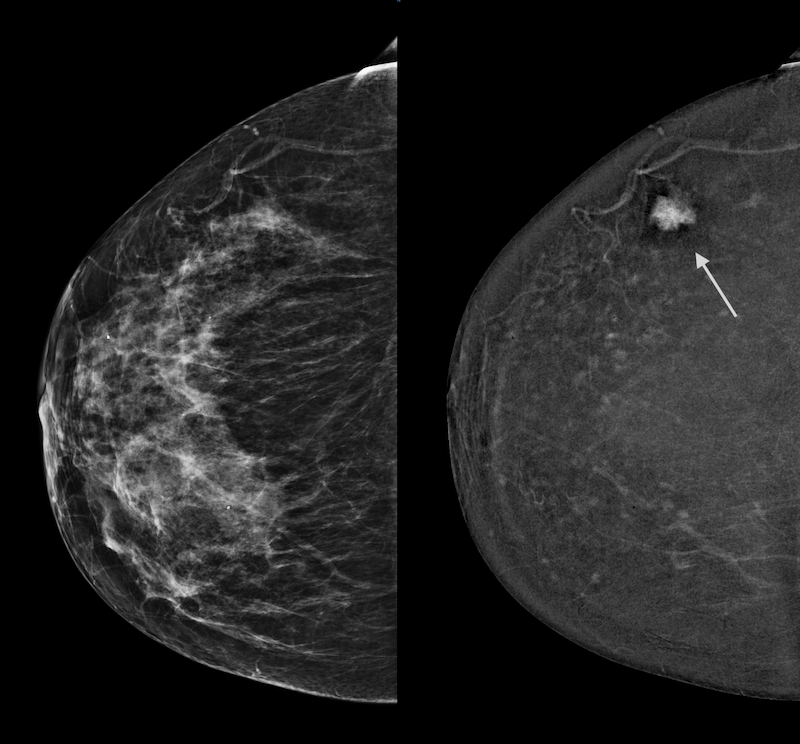

Here’s an example: 2 images of the same breast, on the same day. Traditional mammogram on left: the cancer is not visible. CEM image on the right is not limited by the dense tissue and highlights the cancer (arrow).